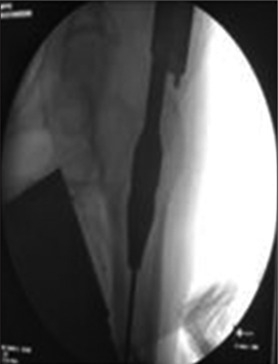

Background: Proximal Femoral Nailing (PFN) and Proximal Femoral Nailing Anti-rotation (PFNA 2) are both intra-medullary implants having 6 degrees of proximal valgus angulation. The helical blade compact the cancellous bone in femoral head when it is driven inside.

Materials and methods: The study was conducted from October 2021 to September 2022 which included 76 patients of unstable intertrochanteric fractures of femur.

Conclusion: PFNA 2 significantly reduces the operative time and blood loss compared to PFN. However Both PFN and PFNA 2 implants offers no statistically significant advantages over each other in terms of fracture unions, functional and radiological outcomes, post-operative complications and recovery outcomes.